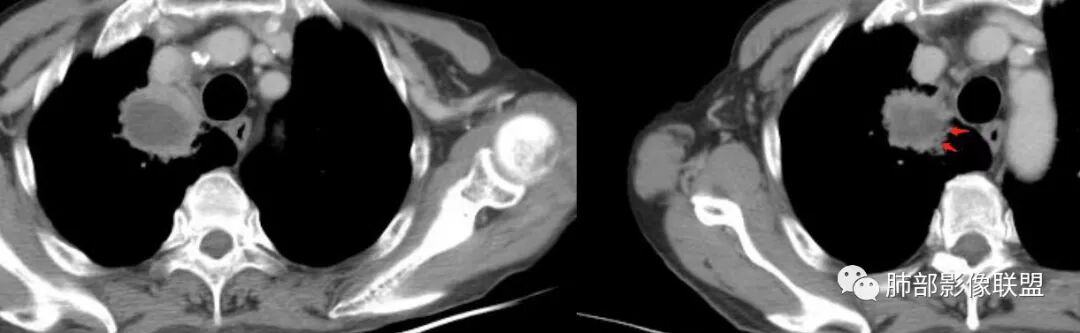

右肺尖肿块,支气管截断,内部坏死,纵膈淋巴结肿大伴坏死,上腔静脉内似有低密度影,治疗后复查空洞形成,主病灶无明显变化。考虑恶性。

临床感染证据明确, 淋巴结薄壁强化也多见于炎性, 病灶气液平坏死,似乎也多见于炎性。 但是,病灶坏死边缘不锐利, 坏死空洞有壁结节, 主要是一月复查,病灶虽然出现气液平, 病灶轮廓却在增大,原来直边消失,鳞癌伴感染可能更大。

首诊,右肺上叶尖段肿块伴坏死,纵隔淋巴结肿大并坏死,坏死边界不光整,后续肿块坏死增加并积气,灶周新发感染,考虑鳞癌合并感染,鉴别肺脓肿

主病灶在右上叶尖段、前段纵隔旁,紧贴胸膜

整体而言:远侧、内侧壁厚

坏死明显,这类膨隆就不支持生长速度不一致所致,而支持坏死朝周围的压力导致边缘的膨隆

这里倒是符合血管的压迫

最让人放心不下的是这里

上腔静脉外面按理没有淋巴结啊

其次:团块影的壁:厚薄不均匀